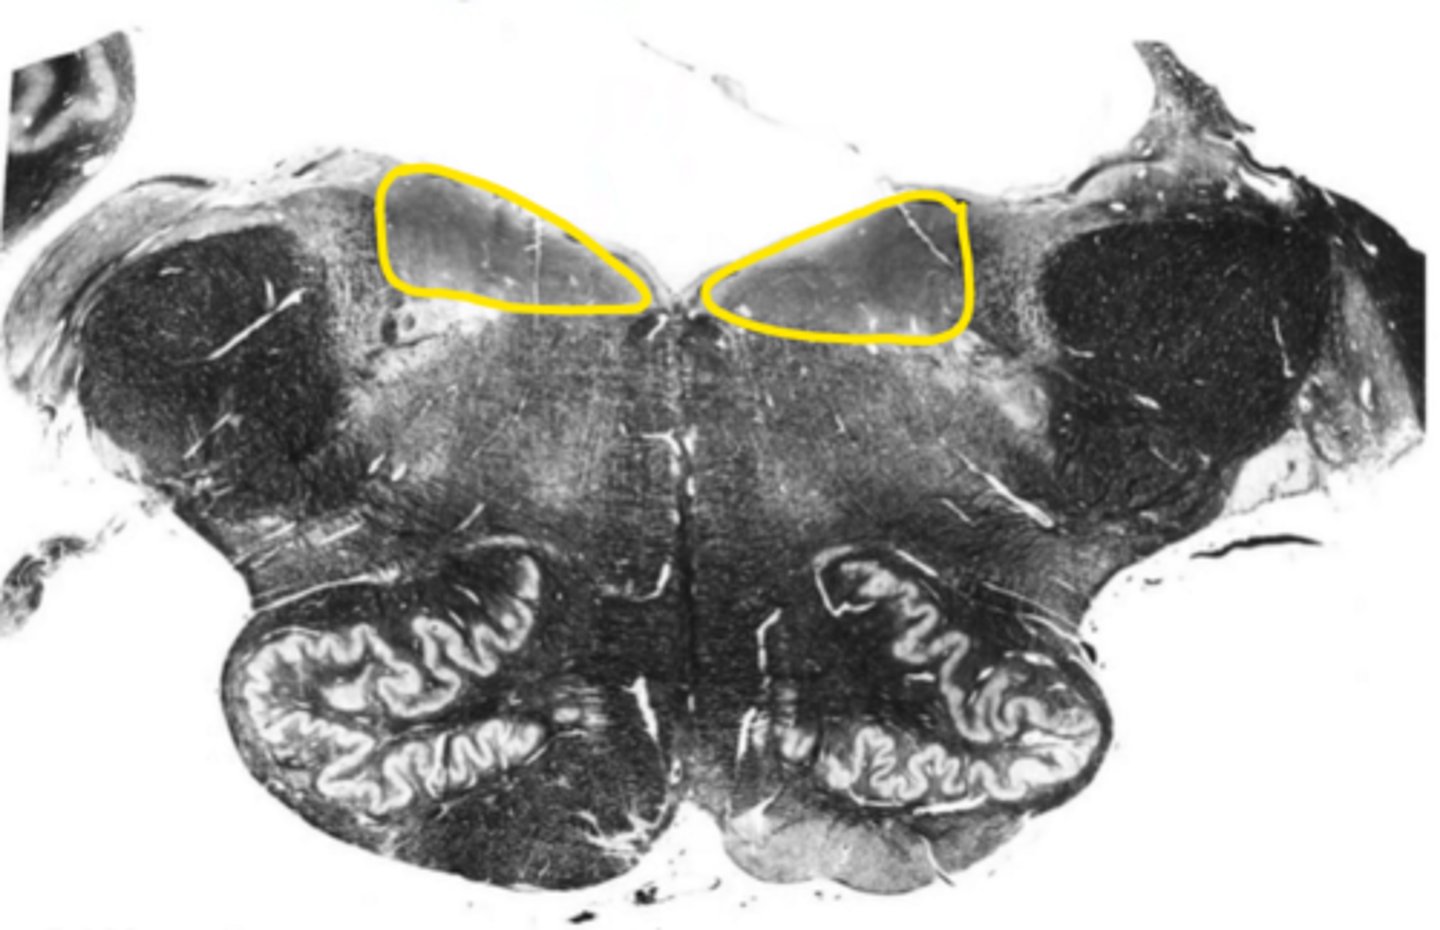

medial lemniscus

ID the structure

corticospinal fibers

pontine nucleus

ID the nucleus

vestibular nucleus

fourth ventricle

ID the space

reticular formation